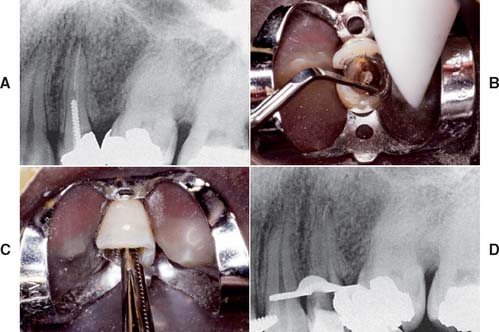

If the coronal structures are largely intact and loading is favorable, as on anterior teeth that are farther removed from the fulcrum (see Chapter 4), a simple filling can be placed in the access cavity (Fig. 12-2A). However, if a substantial amount of coronal structure is missing, a cast post and core is indicated instead (Fig. 12-2B). Molars are often restored with amalgam or a combination of one or more cemented posts and amalgam or composite resin (Fig. 12-2C and D).

Fig. 12-2 A, An anterior tooth with an intact clinical crown can be predictably restored with a composite restoration in the access cavity. B, When most coronal tissue is missing, a cast post and core is indicated to obtain optimal tooth preparation form. C, In mandibular molars, an amalgam foundation is retained by a cemented prefabricated post in the distal canal. D, In maxillary molars, the palatal canal is most often used.